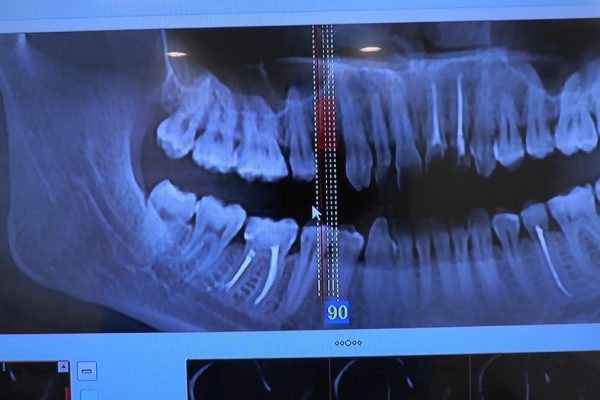

W ostatni weekend czerwca 2018 roku kursanci II Sezonu Preludium Implantologii odbyli piątą, finałową sesję, która w całości podporządkowana była praktyce. W ciągu dwóch dni zabiegowych Lekarze uczestniczący w szkoleniu przeprowadzili szereg zabiegów pod kierunkiem dr n.med. Violetty Szycik. Wszczepili 17 implantów oraz przeprowadzili ekstrakcje i zabiegi regeneracyjne kości. Zabiegi były wykonywane także w sedacji dożylnej z udziałem specjalisty anestezjologii i intensywnej terapii dr Jolanty Grzybowskiej. Preludium implantologii to nowy program edukacyjny dla adeptów implantologii stomatologicznej, którego celem jest wprowadzenie do implantologii poprzez pozyskanie wiedzy w szerokim zakresie i uwzględnieniem szczegółów mających decydujące znaczenie dla powodzenia leczenia implantologicznego. Ale tak jak wszystkie szkolenia w Instytucie Vivadental, w tym wiodące Practiculum Implantologii, zorientowane jest na praktyce i samodzielnym wykonywaniu zabiegów pod kierunkiem Mentora. To najlepsza edukacja w medycynie zabiegowej, a zarazem najlepszy start do implantologii.